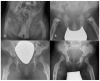

Mucolipidosis type II (MLII) is a rare lysosomal storage disorder caused by defective trafficking of lysosomal enzymes. Severe skeletal manifestations are a hallmark of the disease including hip dysplasia. This study aims to describe hip morphology and the natural course of hip pathologies in MLII by systematic evaluation of plain radiographs, ultrasounds and magnetic resonance imaging (MRI). An international two-centered study was performed by retrospective chart review. All MLII patients with at least one pelvic radiograph were included. A total of 16 patients were followed over a mean of 3.5 years (range 0.2-10.7 years). Typical age-dependent radiographic signs identified were femoral cloaking (7/16), rickets/hyperparathyroidism-like changes (6/16) and constrictions of the supra-acetabular part of the os ilium (16/16) and the femoral neck (7/16). The course of acetabular and migration indexes (AI, MI) significantly increased in female patients. However, in the overall group, there was no relevant progression of acetabular dysplasia with a mean AI of 23.0 (range 5°-41°) and 23.7° (range 5°-40°) at the first and last assessments, respectively. Better knowledge on hip morphology in MLII could lead to earlier diagnosis, improved clinical management and enables assessment of effects of upcoming therapies on the skeletal system.